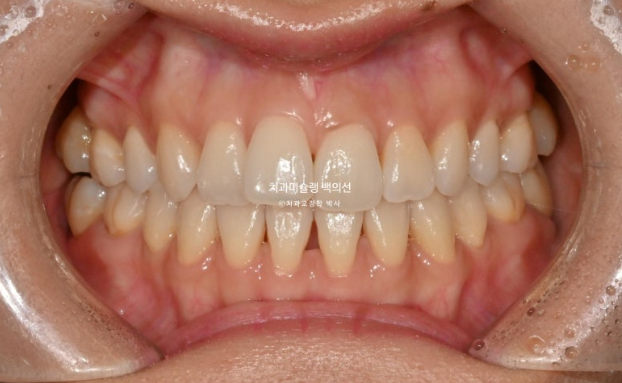

3월부터 5월까지 2달간 7개 장치를 모두 낀 후 모습입니다.

25.05

윗니는 제자리로 잘 들어갔으나 아래 앞니 블랙트라이앵글이 여전히 큽니다.

앞니 배열 완료입니다.

아래 앞니 블랙트라이앵글을 더 없애고자 추가장치 제작에 들어갑니다.

이제 전 후 비교 보겠습니다.

25.03~25.09

깔끔해진 미소가 돋보입니다.